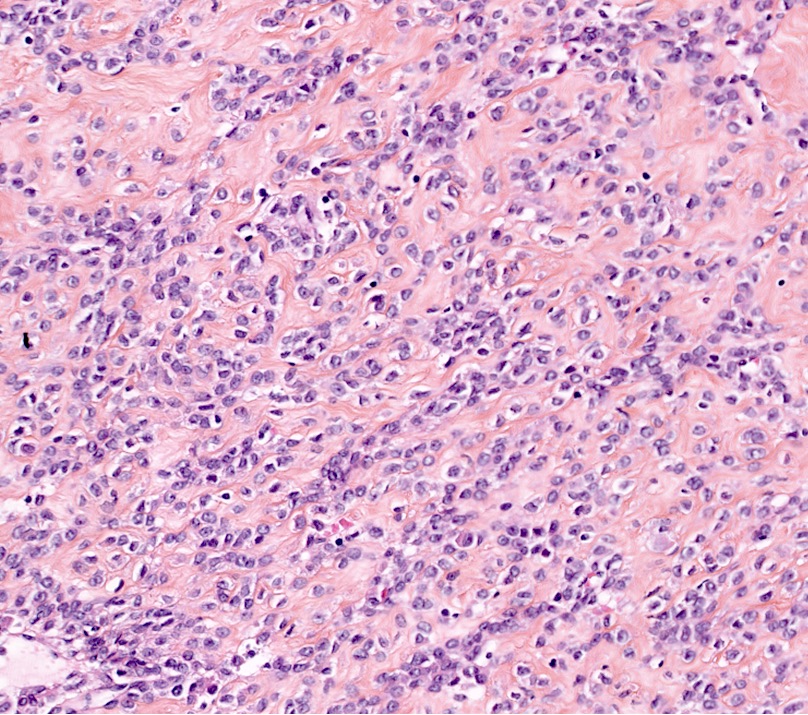

- Conventional / usual leiomyoma (spindle):

- Well defined borders

- Normocellular

- Intersecting fascicles of monotonous spindle cells with indistinct borders, eosinophilic cytoplasm, cigar shaped nuclei (with tapered ends) and small nucleoli

- Atypia: absent or mild

- Mitoses: rare (in general < 5/10 high power fields)

- Blood vessels with thick walls

- With or without infarct type necrosis, hyalinization, calcification, cystic change